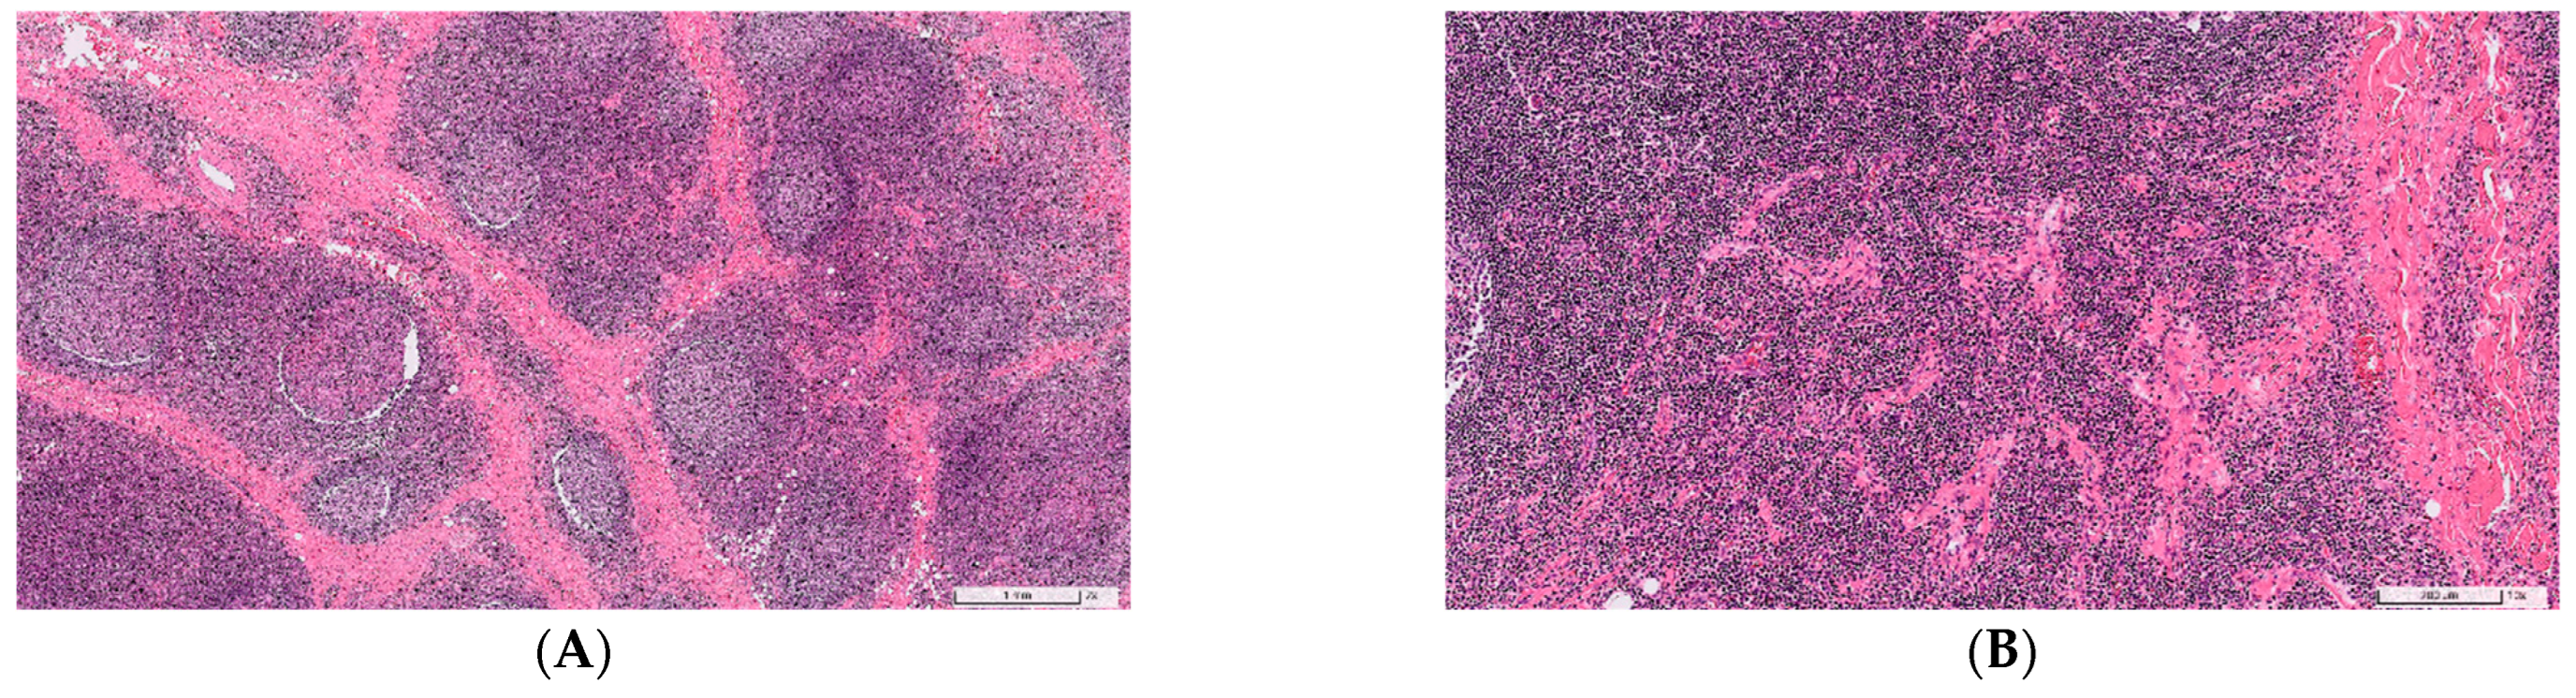

| Histological features | ||||

| Lymphoplasmacytic infiltration | Almost always (98%) [7,12,17] | Almost always (95%) [12,17,22] | Positive | Positive |

| Lymphoid follicular hyperplasia | Almost always (95%) [12,17] | Almost always (92%) [12,17] | Positive | Positive |

| Eosinophil infiltration | Almost always (100%) [7,12] | Sometimes (49%) [12,19,22] | Positive | Positive |

| Eosinophilic abscess | Frequently (74%) [12,17] | Rarely (1%) [12,17] | Positive | Negative |

| Proliferation of postcapillary venules | Frequently (82%) [7,12] | Sometimes (55%) [12] | Positive | Positive |

| Stromal fibrosis | Frequently (80%) [7,12,17] | Frequently (82%) [12] | Positive | Positive |

| Storiform fibrosis | Rarely (6%) [7,12,17] | Sometimes present (49%) [10,12,17,22] | Negative | Negative |

| Obliterative phlebitis | Rarely (1%) [7,12] | Occasionally present (22%) [10,12,19,22] | Negative | Negative |

| IgG4 (+) plasma cell ≥ 50/HPF | Occasionally (36%) [7,12] | Almost always (100%) [12,17,19] | Positive | Positive |

| IgG4/IgG (+) plasma cell ratio ≥ 40% | Occasionally (39%) [7,12] | Almost always (100%) [12,17,19] | Positive | Positive |